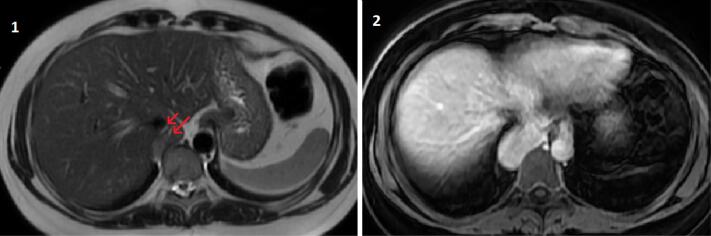

We present a case with an intrathoracic caudate lobe in a 45-year-old woman who referred with a complaint of nonspecific chest pain. She denied previous history of trauma or surgery. Computed tomography (CT) pulmonary angiography showed a paravertebral, soft tissue mass which raised suspicion of a pleural tumor. In the coronal plane, the mass was protruding to the abdomen and had similar density with liver. Magnetic resonance imaging confirmed the diagnosis.

我们提出一个病例与胸内尾状叶在一个45岁的妇女谁提到投诉非特异性胸痛。她否认有外伤或手术史。CT肺血管造影显示椎旁软组织肿块,怀疑为胸膜肿瘤。在冠状面,肿块向腹部突出,密度与肝脏相近。磁共振成像证实了诊断。